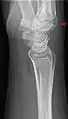

Additional images

Carpal boss in plain X-Ray.